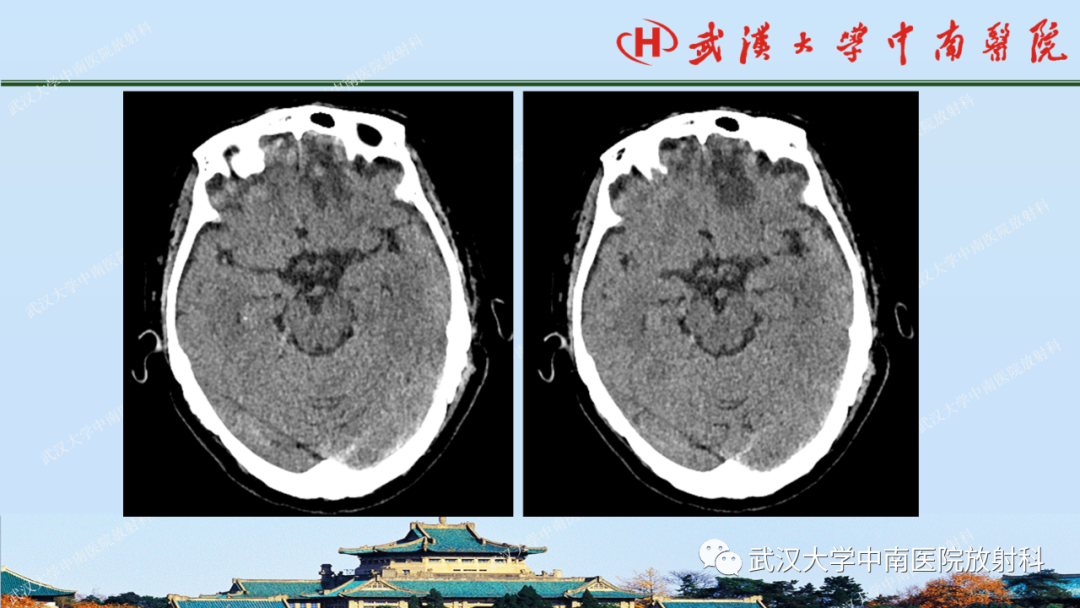

【PPT】脑外伤影像学诊断